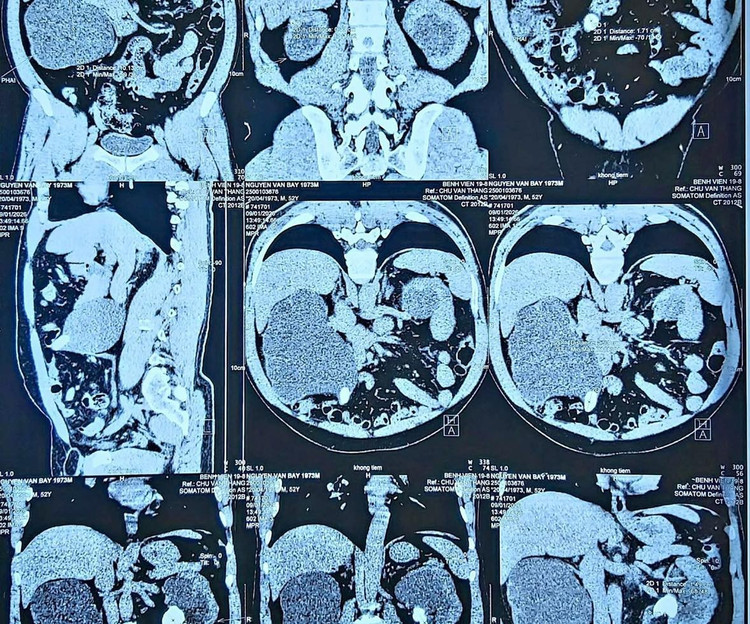

Trên phim CT: Thận trái giãn mỏng, gần như mất hoàn toàn chức năng; Thận phải còn hoạt động, nhưng đã suy giảm nặng.

Trên phim chụp CT: Thận trái giãn mỏng, gần như mất hoàn toàn chức năng; Thận phải còn hoạt động, nhưng đã suy giảm nặng - Ảnh BVCC